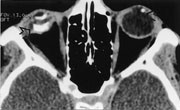

Nøyaktig lokalisasjon av intraokulære og intrabulbære fremmedlegemer er nødvendig preoperativt, og CT er en velegnet metode (9). Artefakter fra metalliske fremmedlegemer kan imidlertid gi inntrykk at fremmedlegemet er større enn dets virkelige mål (fig 6). MR er ofte kontraindisert fordi det sterke magnetfeltet kan bevege magnetiske fremmedlegemer og gi komplikasjoner.

CT gir best fremstilling av bein. Hvis det imidlertid er anamnestiske holdepunkter for at fremmedlegemet er av tre eller ikke-magnetisk materiale, er MR det beste valget. Til nøyaktig lokalisering av fremmedlegeme kreves snitt i to plan, noe som øker undersøkelsestiden og utsetter pasienten for større strålebelastning. Spiral-CT har mange fordeler i denne sammenheng – det gir kortere undersøkelsestid, reduserer stråledosen og gir høy kvalitet der bilder kan rekonstrueres i flere plan. CT har for en stor del erstattet tidligere ordinære røntgenbilder.